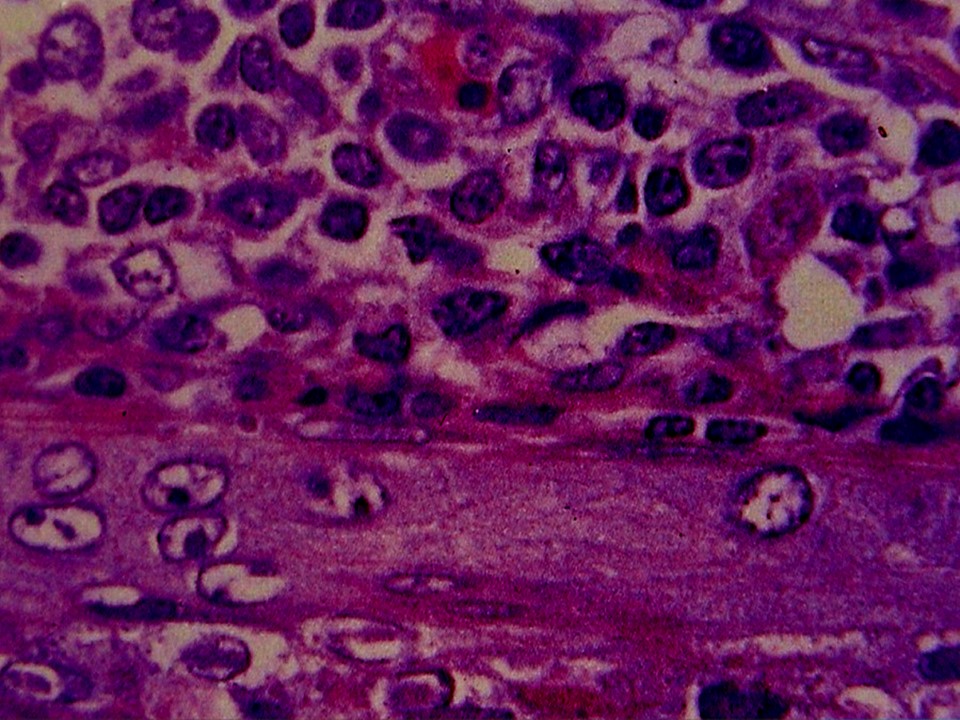

疾病中文名稱:馬立克病

疾病英文名稱:Marek's disease

影像說明:翼神經受侵犯而翅膀下垂,坐骨神經受侵犯呈劈腿狀